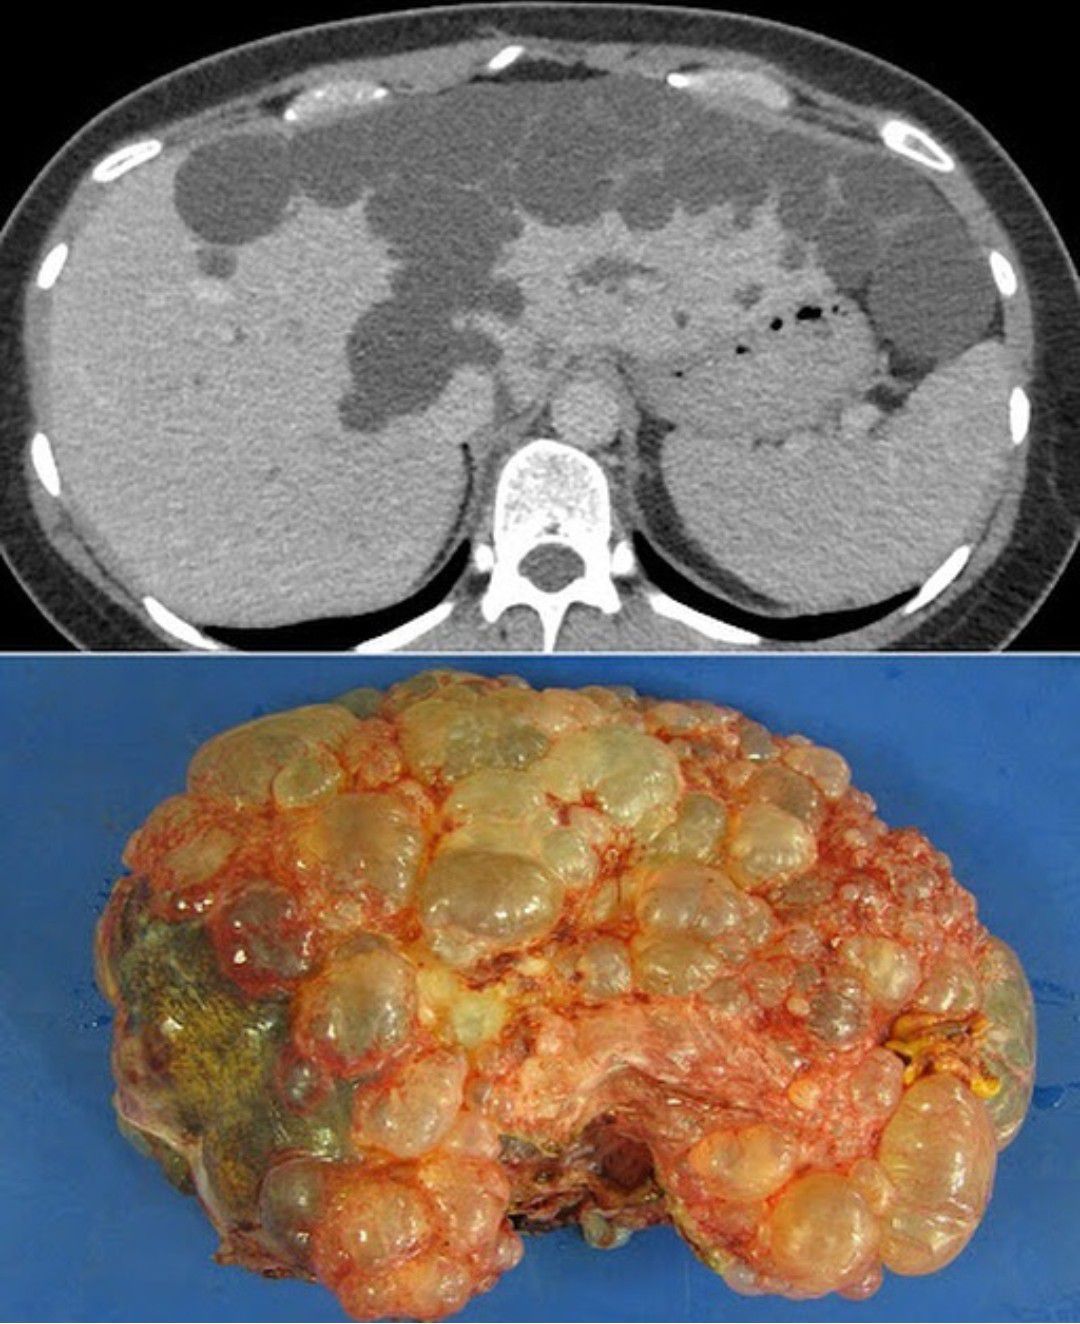

Polycystic liver disease is a rare condition that causes cysts to grow throughout the liver. This patient presented with upper abdominal pain. An abdominal ultrasound was arranged and showed a large number of cysts in the liver. Subsequent CT scan demonstrates multiple cysts of varying sizes, predominantly involving the left lobe of the liver. This patient also had multiple cysts in both kidneys. These are the appearances of polycystic liver disease. As the patient was very symptomatic, a left hemihepatectomy was performed. The resected left lobe is shown here, and correlates nicely with the CT image above it. Polycystic liver disease is a hereditary, autosomal dominant condition that is more common in women and, in around half of patients, is associated with polycystic kidney disease, as in this patient. The majority of patients are asymptomatic however in some patients the cysts cause abdominal pain, distension, or early satiety (due to mass effect on the adjacent stomach). Rarely, the condition can cause hepatic failure and portal hypertension. Patients may also present with acute abdominal pain due to hemorrhage into a cyst, or rupture of a superficial cyst into the peritoneal cavity.